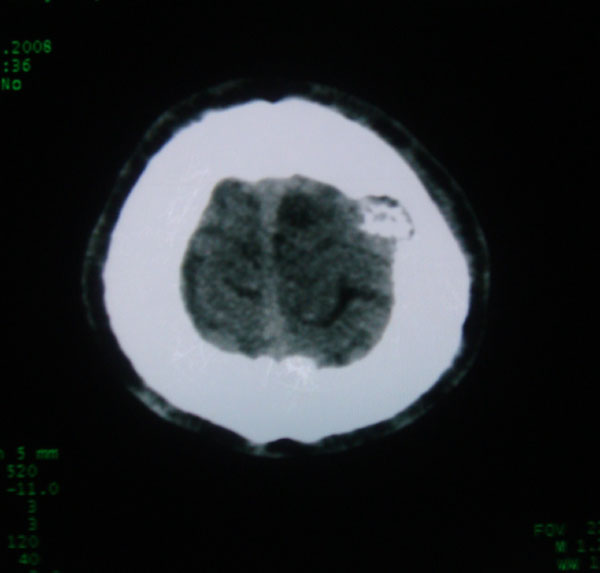

以下是引用拾荒者在2008-6-7 13:05:00的发言:[br]左侧顶骨局限性骨质缺损,边缘锐利,无硬化边,周围软组织轻度肿胀,无明显软组织肿块及骨膜反应,考虑嗜酸性肉芽肿可能。